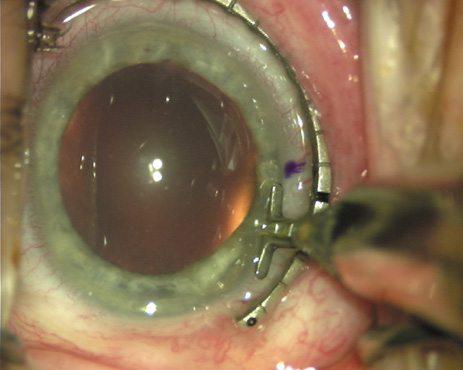

Case 2 is a 79-year-old woman who presented with a very dense left cataract. Her refraction was recorded at −2.25 +2.75 × 125 with a difficult end point. Her manual keratometry and topography measurements were consistent and revealed slightly less than 1.75 D at 120 degrees. Because of the questionable refraction, greater value was placed on the corneal measurements. Based upon the cataract nomogram, the plan was for paired LRIs of 40 degrees to be placed over the steep 120-degree axis (Figs. 1219).

Fig. 16. The starting point of the opposing incision is determined. (Reprinted from Hardten DR, Lindstrom RL, Davis EA. Phakic Intraocular Lenses: Principles and Practice. Thorofare, NJ: SLACK Incorporated, 2004, with permission.)